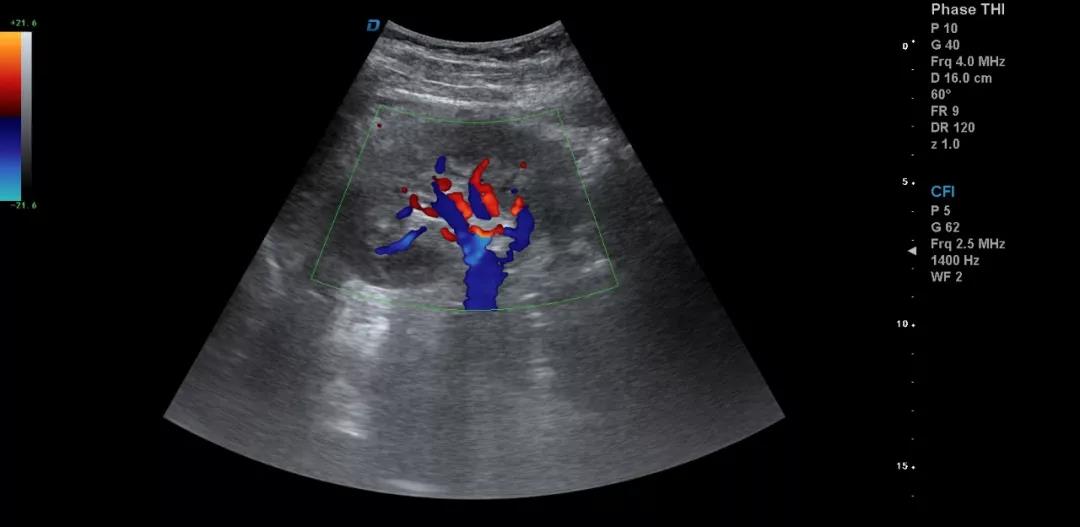

一個正確的診斷往往是醫學理論、臨床經驗和正確思維方法三者有機結合的結果。醫用B超機作為一種常見的檢查儀器,對某些疾病的診斷具有明顯優勢,已成為一種便捷、無創、有效的檢查手段。因此,超聲診斷的目標就是減少漏診、誤診,或為最終診斷提供更多更有價值的信息。

3.注意在工作中積累超聲資料

典型圖片、經典病例圖片、動態影像資料積累的多了分析總結之后就提高了。疑難病例資料積累后,可以隨訪病人,然后總結得到的臨床資料和病理結果。

有了手術結果和病理才會有真正的提高。按器官、按系統、按學科進行總結每一個、每一類疾病正常及異常圖片就是知識的積累。